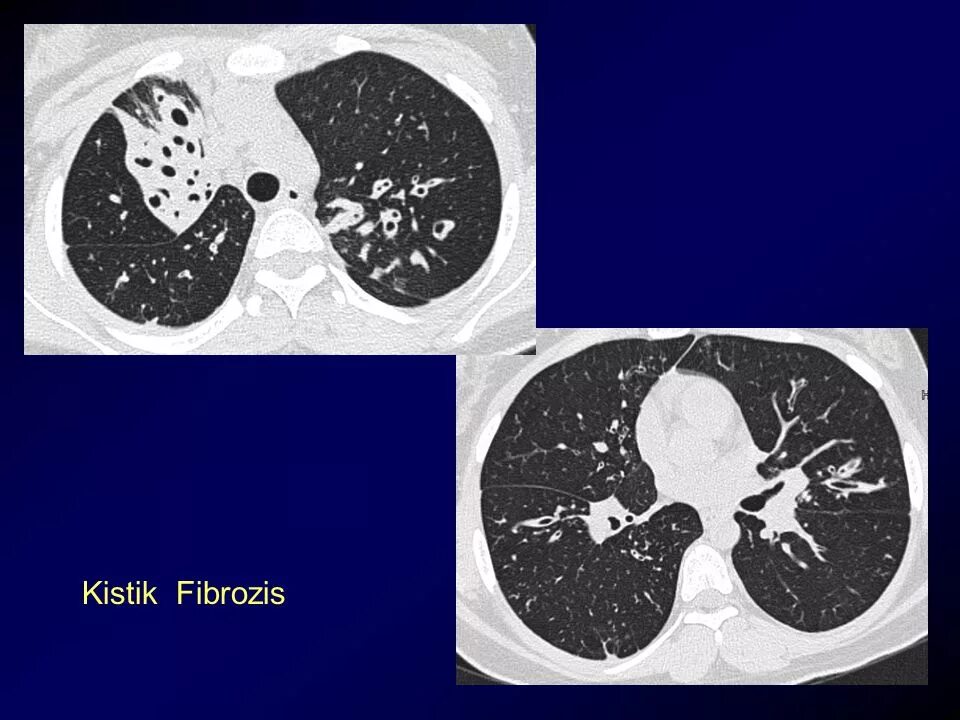

Фиброз кт